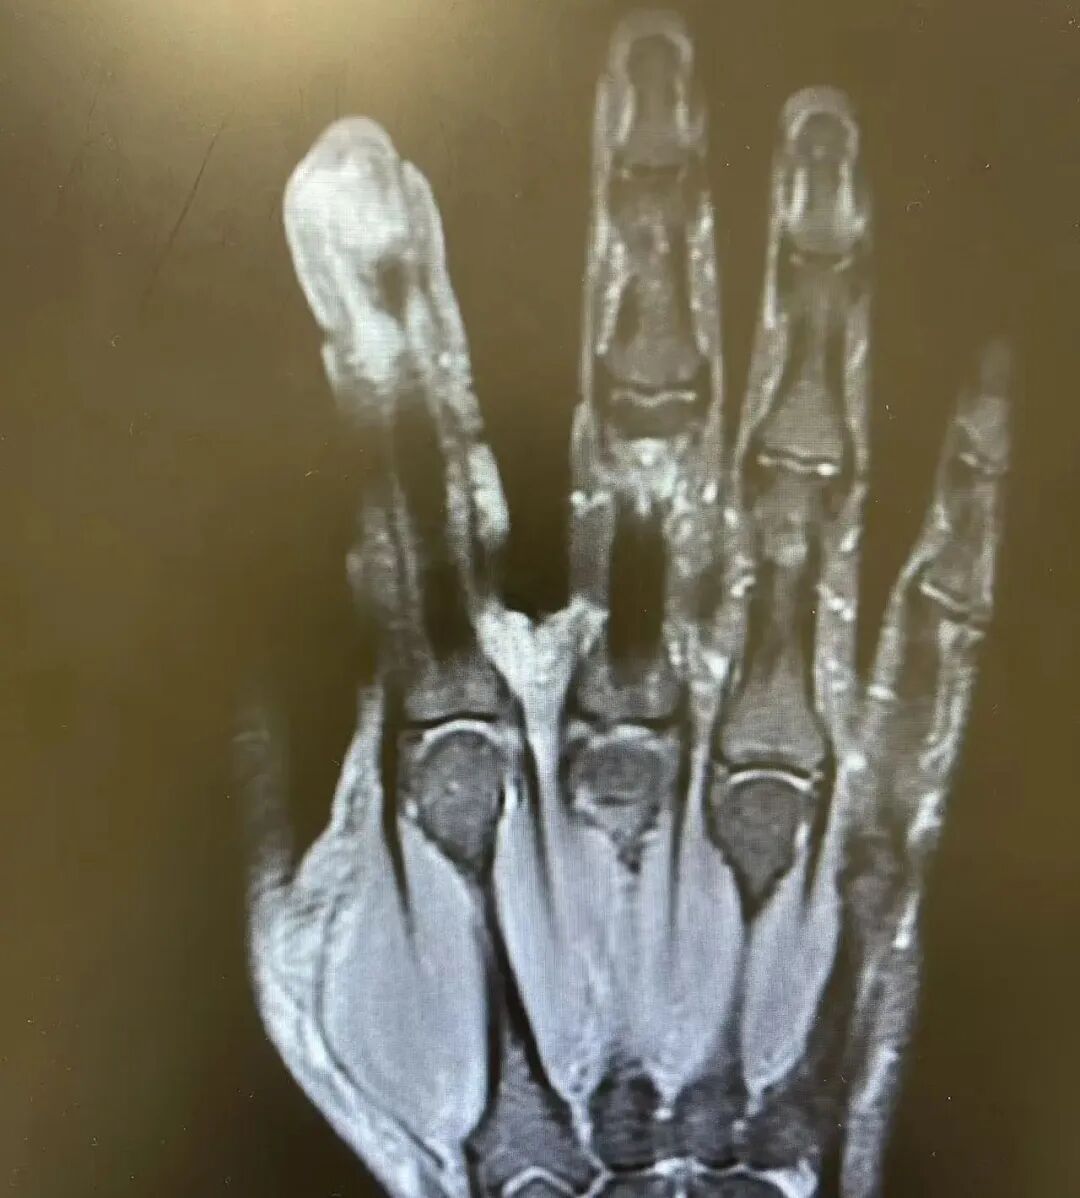

经过一系列检查,李哥破溃的左手指尖严重感染,厌氧消化链球菌顺着破损处钻到骨头里,引发了严重骨髓炎,“再晚一步,就会有截肢风险!”卢荟主任医师建议李哥必须手术清创再配合抗感染治疗才能脱险。因为随着骨髓炎细菌入血,还会出现感染性休克的致命风险!

手术室里,卢荟帮李哥“刮掉”坏死的骨头碎片,清除坏死的肌肉与皮肤。

经过专家团队的精心救治,李哥的手指保住了,但因感染已经严重破坏了他的关节,手指末节的活动今后会存在一定的受限,很难恢复如原来那般灵巧。